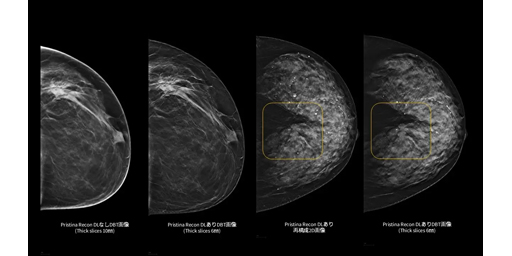

背景 デジタル乳房トモシンセシス(DBT; 3Dマンモグラフィ)は、2次元のデジタルマンモグラフィ(DM)と比較して病変の視認性が高く、特に高濃度乳房でDMよりも有効性が高いと考えられている。ただし、…

背景 デジタル乳房トモシンセシス(DBT)は複数回のX線撮影を疑似的な3次元画像として再構成することにより、乳腺の重なりを軽減し、2次元のデジタルマンモグラフィ(DM)と比較して病変を、より正確に捉え…

背景 デジタル乳房トモシンセシス(DBT)は乳腺の重なりを軽減し、高濃度乳房に対して従来マンモグラフィより有効と考えられている。 University of California, San Franc…

背景 デジタル乳房トモシンセシス(DBT)は、乳腺の重なりを軽減し、従来マンモグラフィよりも高感度であることが示唆されている。スウェーデンLund UniversityのJohnsonらは、40~74…